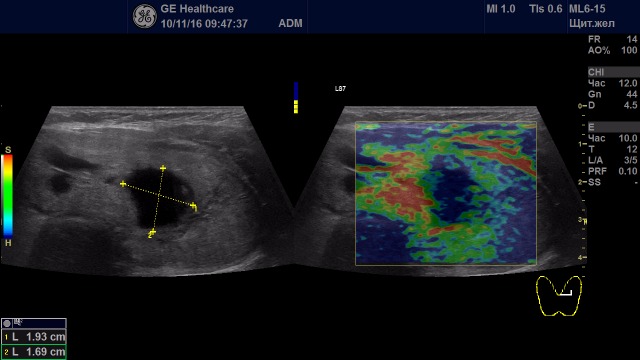

Образования с неудовлетворительной эластичностью (тип IV-V)